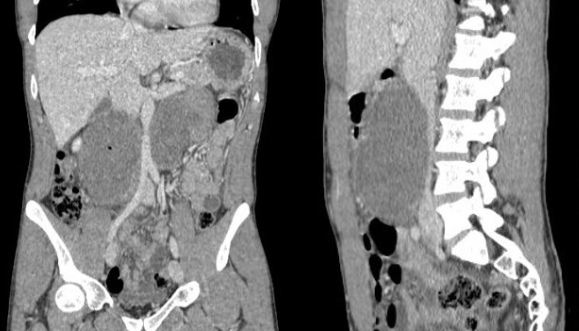

Historia clínica: Antecedentes personales: no enfermedades previas de interés, no antecedentes quirúrgicos, no alergias conocidas. Hábitos tóxicos: tabaco 1 paquete/día; cocaína, cannabis y TUSI, uso recreativo; alcohol, ocasional. Anamnesis: Paciente masculino de 28 años de aspecto atlético, que consulta por dolor abdominal de inicio súbito en epigastrio y mesogastrio, EVA 8/10, de 4-5 horas de evolución, sin otros síntomas asociados. Refiere consumo de anabolizantes (anabolizantes del GYM: boldenona, testosterona), además de proteína y creatina. Exploración: TA: 155/100 Abdomen: RHA presentes y conservados, abdomen blando, depresible, doloroso a la palpación superficial ni profunda en mesogastrio e hipogastrio. Sin signos de irritación peritoneal. Pruebas complementarias: Ecografía A pie de cama Se realiza barrido con sonda convexa; se observan dos masas lobuladas en la región del mesogastrio, heterogéneas e hiperecogénicas, derecha con área anecoica, diámetro aproximado de 16 cm, con paredes bien definidas, que no capta con Doppler. Tras control del dolor, se decide remisión al hospital de referencia, donde se completa estudio con analíticas, TAC y BAG de las lesiones: Analíticas: LDH 1,361 U/L (<300), PROTEÍNA C REACTIVA 17,19 mg/dL (<0,5), BETA-2 MICROGLOBULINA 2.903 µg/L (<2,5). BETA HCGMT 5,43 mU/mL (<5). TAC: CONCLUSIÓN: Las lesiones descritas presentan aspecto inespecífico, debiendo plantear dentro de diferentes posibilidades diagnósticas que correspondan a extensos conglomerados ganglionares o lesiones infiltrativas primarias/secundarias, incluso debiendo plantear como posibilidad tumores germinales. BAG de las lesiones eco guiada: Anatomía patológica SEMINOMA

Juicio clínico: Seminoma con metástasis ganglionar no visceral.